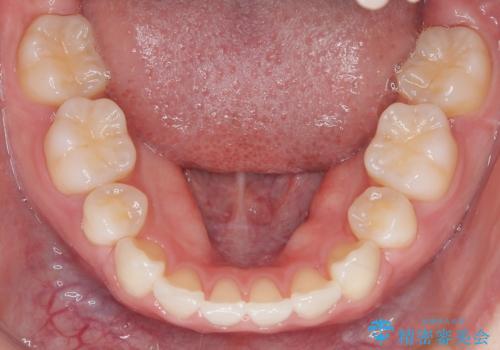

- 出っ歯を主訴に来院されました。今回は4番の歯を4本抜歯をし、ワイヤー矯正にて治療しました。

抜歯矯正のため2年を予定してましたが、予定よりも早く終わることができました。また口元も下がり、かみ合わせも改善しました。